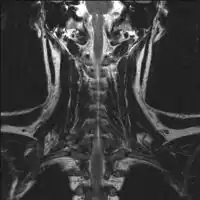

2.a. MRI neck (side view): solitary plasmacytoma C6 -

2.b. MRI neck (view from behind): solitary plasmacytoma C6